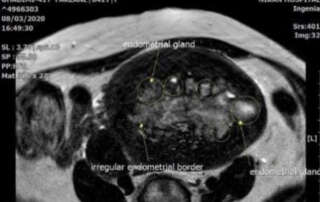

Extra-ordinary High Cancer antigen 125 (CA-125) level in a 41 year-old patient with adenomyosis